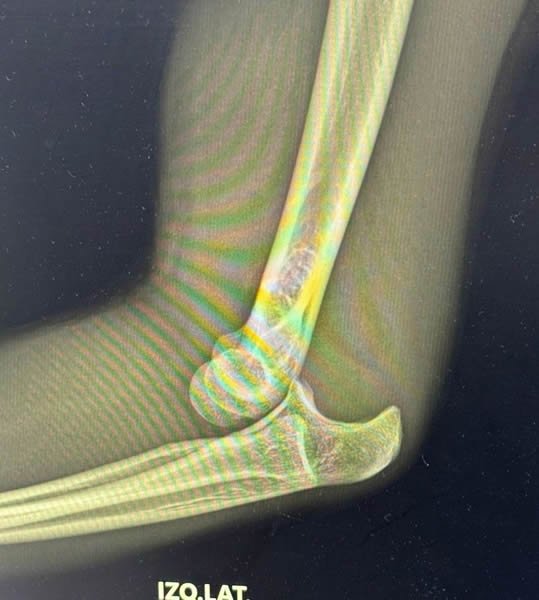

La empresa Espectáculos Monterrey (EMSA) informa que, el matador de toros neoleonés Sergio Garza sufrió un percance durante sus actividades de preparación, derivando en una luxación posterior, contusión del nervio cubital y lesión de los ligamentos de la cápsula articular del codo izquierdo, por lo que, en consecuencia, le impedirá actuar en la corrida de este domingo 9 de noviembre de 2025 en el coso Monumental -Lorenzo Garza- de la ciudad de Monterrey, Nuevo León.

Sergio Garza se recupera de la lesión en el codo izquierdo, pero, no podrá torear este domingo ante su gente / Fotos EMSA